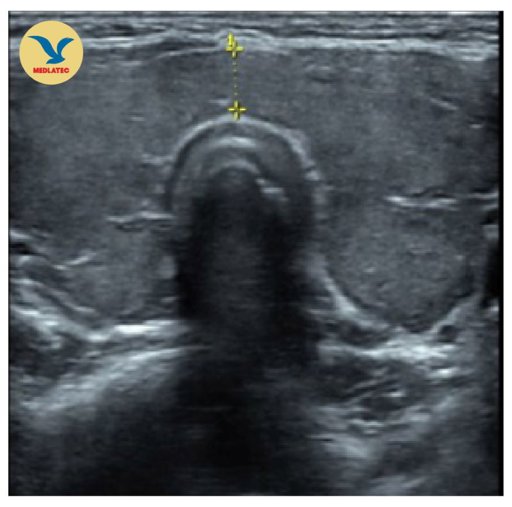

Trẻ nữ 11 tuổi đến thăm khám tại Bệnh viện Đa khoa MEDLATEC với tình trạng vùng cổ to bất thường và được chẩn đoán viêm tuyến giáp Hashimoto giai đoạn suy giáp. Đây là bệnh lý tự miễn phổ biến mắc phải ở trẻ em và thanh thiếu niên, nếu không được phát hiện, điều trị kịp thời sẽ ảnh hưởng đến phát...